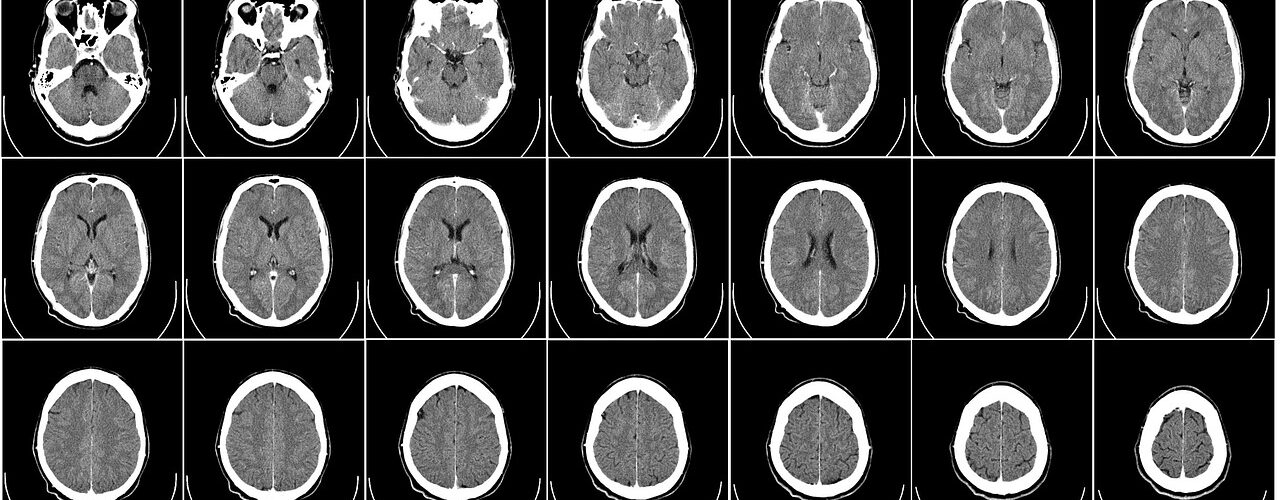

Week1 Day3 神経系、CT

全身にわたる系統から、神経系(脳は神経解剖学で)。

CTとDICOMビューア。今日インストールしよう! 小一時間以上掛かります。ファイル容量も1GBを超えます。